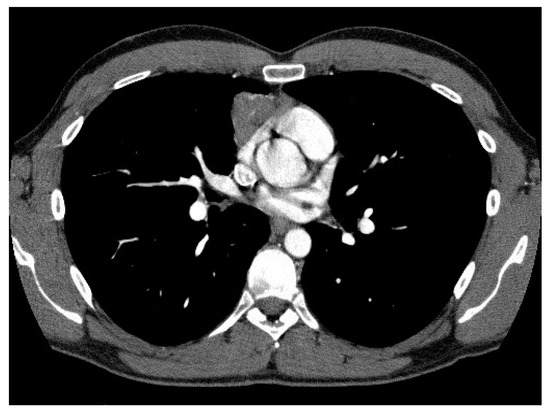

2.3. CT Scan Features and Image Interpretation

3.3. Correlation of CT Scan Parameters, Histology and Staging